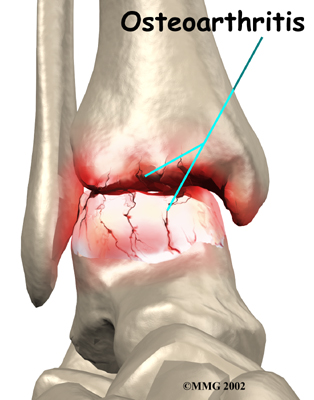

OA is usually considered a type of degenerative arthritis, or wear-and-tear arthritis. Doctors consider OA pretty much the same whether it appears years after an injury to the joint or whether it appears without any history of injury. It behaves more or less the same way.

Injury to a joint, such as a bad sprain or fracture, can cause damage to the articular cartilage. The cartilage can be bruised when too much pressure is exerted on it. This damages the cartilage, although if you look at the surface it may not appear to be any different. The injury to the material doesn't show up until months later. Sometimes the cartilage surface is damaged even more severely, and pieces of the cartilage are ripped from the bone. These pieces do not heal back and usually must be removed from the joint surgically. If not, they may float around in the joint, causing the joint to catch and be painful. These fragments of cartilage may also do more damage to the joint surface.

Once this cartilage is ripped away, it does not normally grow back. Unlike bone, holes in the surface are not simply replaced by the cartilage tissue around the hole. Instead the defects are filled with scar tissue. The scar tissue that forms is not nearly as good a material for covering joint surfaces as the cartilage it replaces. It just can't support weight and isn't smooth like true articular cartilage.

An injury to a joint, even if it does not injure the articular cartilage directly, can alter how the joint works. This is true for a fracture where the bone fragments heal differently from the way they were before the break occurred. It is also true when ligaments are damaged that lead to instability in the joint. When an injury results in a change in the way the joint moves, the injury may increase the forces on the articular cartilage. This is similar to any mechanical device or machinery. If the mechanism is out of balance, it wears out faster.

Over many years this imbalance in the joint mechanics can lead to damage to the articular surface. Since articular cartilage cannot heal itself very well, the damage adds up. Finally, the joint is no longer able to compensate for the increasing damage, and it begins to hurt. The damage occurs well before the pain begins.

Symptoms

Pain is the main problem with arthritis of any joint. This pain occurs at first only related to activity. Usually, once the activity gets underway there is not much pain, but after resting for several minutes the pain and stiffness increase. Later, when the condition worsens, pain may be present even at rest. The pain may interfere with sleep. The joint may swell, fill with fluid, and feel tight, especially following increased activity. As the articular cartilage starts to wear off the joint surface, the joint may squeak when moved. Doctors refer to this sound as crepitation.

OA will eventually affect the motion of a joint. The joint becomes stiff and loses flexibility. Certain movements can become painful, and it may become difficult to trust the joint to hold your weight in certain positions. The body has a pain reflex such that when a joint is put into a position that causes pain the muscles around the joint may stop working without warning. This reflex can cause a person to stumble or even fall when arthritis affects the ankle joint.

When OA has reached a very severe stage, the bone itself under the articular cartilage may become worn away. This can lead to increasing deformities around the joint. In the final stages, the alignment of the bones can begin to form odd angles where they meet at the joint.